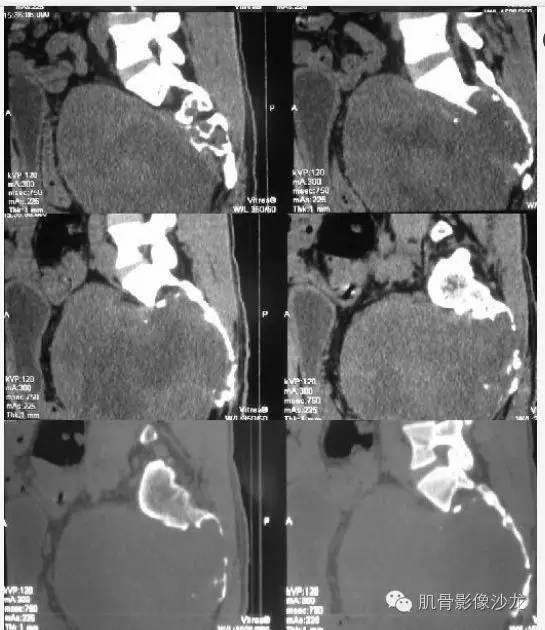

【病例】骶骨神经纤维瘤一例CT影像表现

软组织范围大于骨质破坏,向盆腔方向生长远远大于向背侧,所以考虑软织来源

骶骨处病变似有膨胀的感觉,我倾向于来源于骨,

破坏连续有骨质硬化边,提示破坏修复同时进行,倾向良性生物学行为

来源于骶骨,脊索瘤可能性大

病史:32岁,男性,大小便困难2年,加重伴左侧腰骶部疼痛2个月。

病理:骶骨神经纤维瘤,细胞生长活跃伴局部细胞异型性。